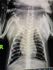

Вопрос ветеринарам по рентг. снимку собаки

Собака простужена, более 2х недель кашель. Вялый.

Подскажите, пожалуйста, на снимке Вы видете воспаление?

Сегодня сказали, что похоже на новообразование....Плачу...